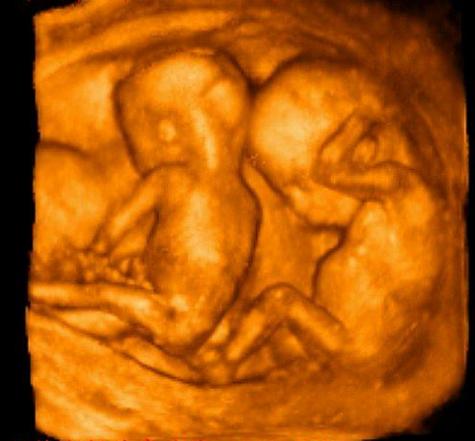

雯雯剛結婚就懷孕了,第一次做B超的時候醫生告訴雯雯肚中的是雙胞胎,老公高興壞了,趕緊給家人報喜。婆婆知道後更是喜上眉梢,剛過門的媳婦一下就懷孕了,而且一下就來兩個,省去了二胎的煩惱。

雯雯婆家從上一代開始就都是男孩,到了雯雯老公這代還是都是男孩,雯雯婆婆整天面對一家這下好,雯雯一下懷了兩個,肚中至少有一個女孩吧!雯雯婆婆喜滋滋地想。可能是要女心切,雯雯的嫂子還特意去私立醫院找人給看了男女,醫生說是兩個女孩,這下可把雯雯家人高興壞了,都嚷嚷著要給小公主們準備禮物。雯雯婆婆沒事就逛母嬰店,買了一堆粉色的小衣服,家人也一起為小公主們佈置了粉嫩嫩的嬰兒房,全家人都對小公主們翹首以待。